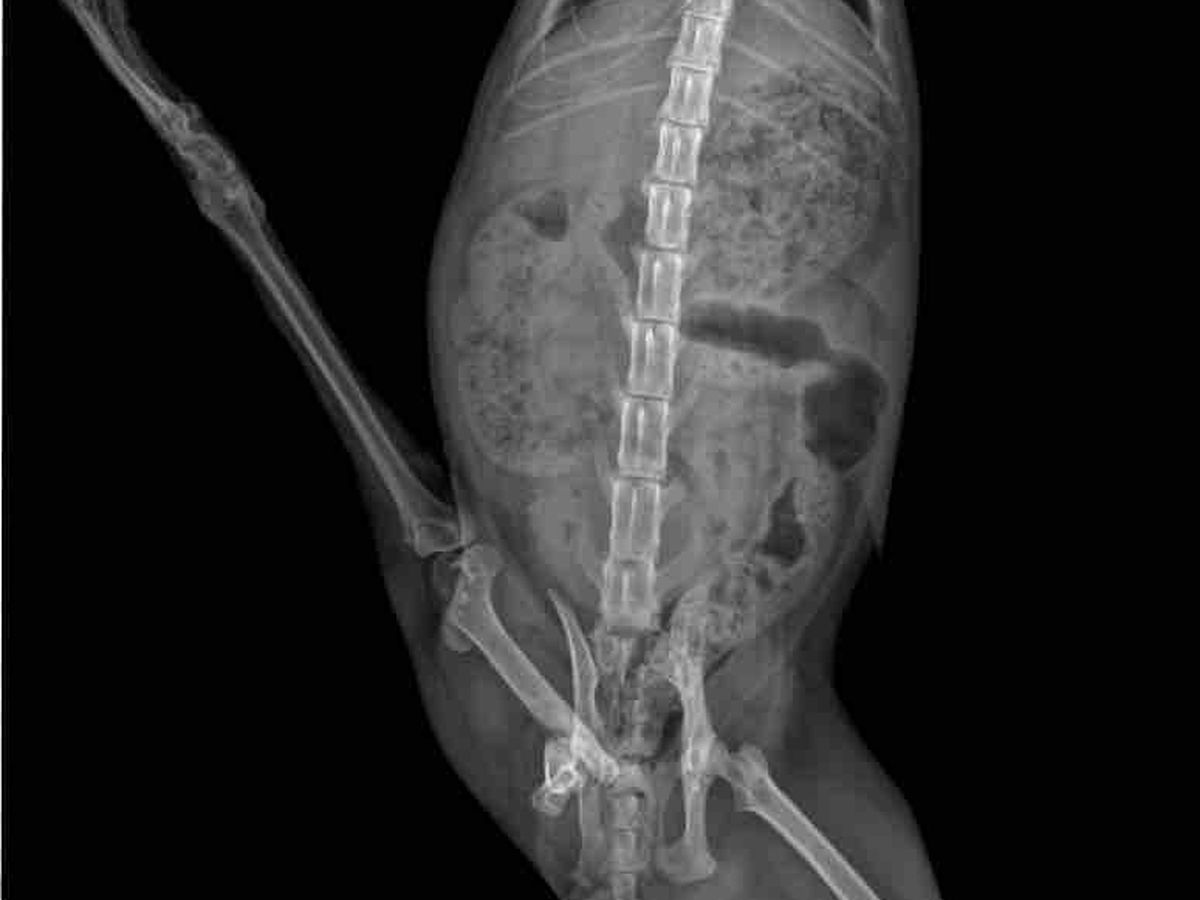

We believe his right rear leg got caught in something – it is non functioning and non weight bearing. He also has a huge gash on that paw.

Artemis will be seen by a vet and xrayed so we can figure out what care is needed going forward. We will also take care of his neuter, vaccinations and combo test.